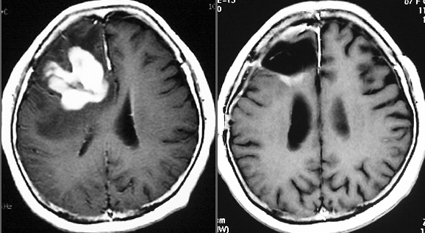

40グレイの全脳照射だけだと脳萎縮と認知機能低下が生じる

1990年代に放射線治療をした古い例です。定位生検術の後で全部の脳に40グレイという線量を照射しました。左から2番目の写真で腫瘍は消えています。でも,6ヶ月後の3番目の写真では脳がやせてきています(脳萎縮)。患者さんの精神機能は著しく低下しました(いわゆる認知障害)。4番目の写真は治療後8ヶ月目のものですが,すでに左側に小さな再発が見られます。全部の脳にあてる放射線の量はできる限り少ない方がいいのです。2017年時点では30グレイというのが標準的線量です。

開頭手術だけでは治らない

開頭手術で全部取ったといわれて紹介された例です。でも右側の写真ではほんの少し残っているようです。この後で化学療法と放射線治療をしました。

開頭腫瘍摘出術をすると化学療法の開始の時期が遅れますし,それを待っている間にも再発してしまうことがあります。また,手術でたくさんとっても治る確率が高くなる病気ではないので,利益はとても少ないと言えます。定位脳手術では取りそこなうことがあるから,小さな開頭手術をするにしても,生検術(ほんの少しだけ腫瘍をつまんで病理診断)するだけです。積極的な腫瘍摘出はしません。